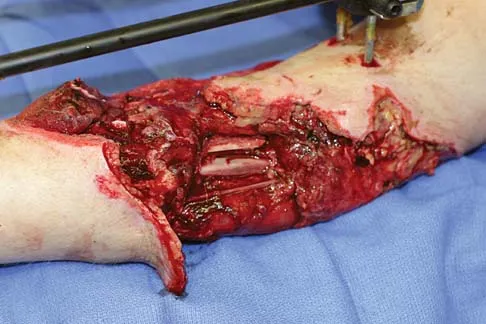

Figures 9a and 9b show the radiographs of a 28-year-old woman who sustained a head injury and a closed injury, without soft-tissue compromise, to her right lower extremity in a motor vehicle accident. Appropriate management of the foot injury should include

Correct Answer: open reduction and internal fixation with screws.

The displaced talar neck fracture should be treated with open reduction and internal fixation using screws. Closed reduction and casting will not maintain position, and percutaneous pinning is not able to maintain reduction to allow union. External fixation and amputation are not necessary for this injury unless there is severe soft-tissue loss.